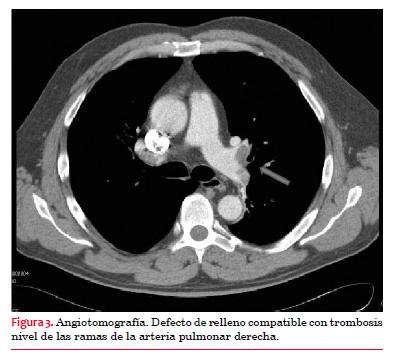

Ecografía Doppler de miembros inferiores: sin evidencias de trombosis venosa profunda.La angiotomografía informa: arteria pulmonar y sus ramas principales levemente dilatadas, la rama derecha de 24 mm y 22 mm la rama izquierda. Defecto de relleno compatible con trombosis a nivel de la rama segmentaria apical del lóbulo superior, de las ramas del lóbulo medio, del sector distal de la rama derecha principal y de las segmentarias del mismo pulmón. Trombosis del sector distal de la rama izquierda de la arteria pulmonar, ramas de la língula y lóbulo inferior izquierdo (figura 3).